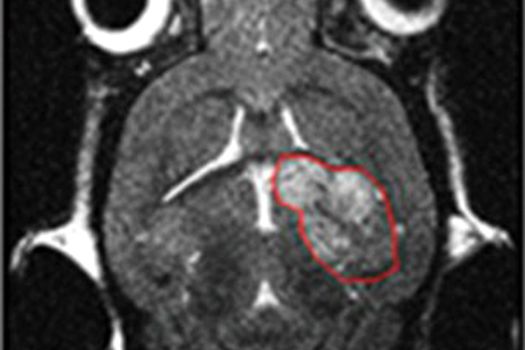

Astfel, oamenii de ştiinţă au fost şocaţi să descopere că medicamentul ce inhibă proteina RAS, bazat pe SHP2, a redus tumorile pe care a fost experimentat cu peste 80%.

Studiul a fost recent publicat în revista Nature Communications, iar acum oamenii de ştiinţă vor lucra cu un chirurg de la Universitatea din Carolina de Nord, pentru a încerca medicamentul pe şoareci ce au tumori pancreatice asemănătoare cu cele ale oamenilor.